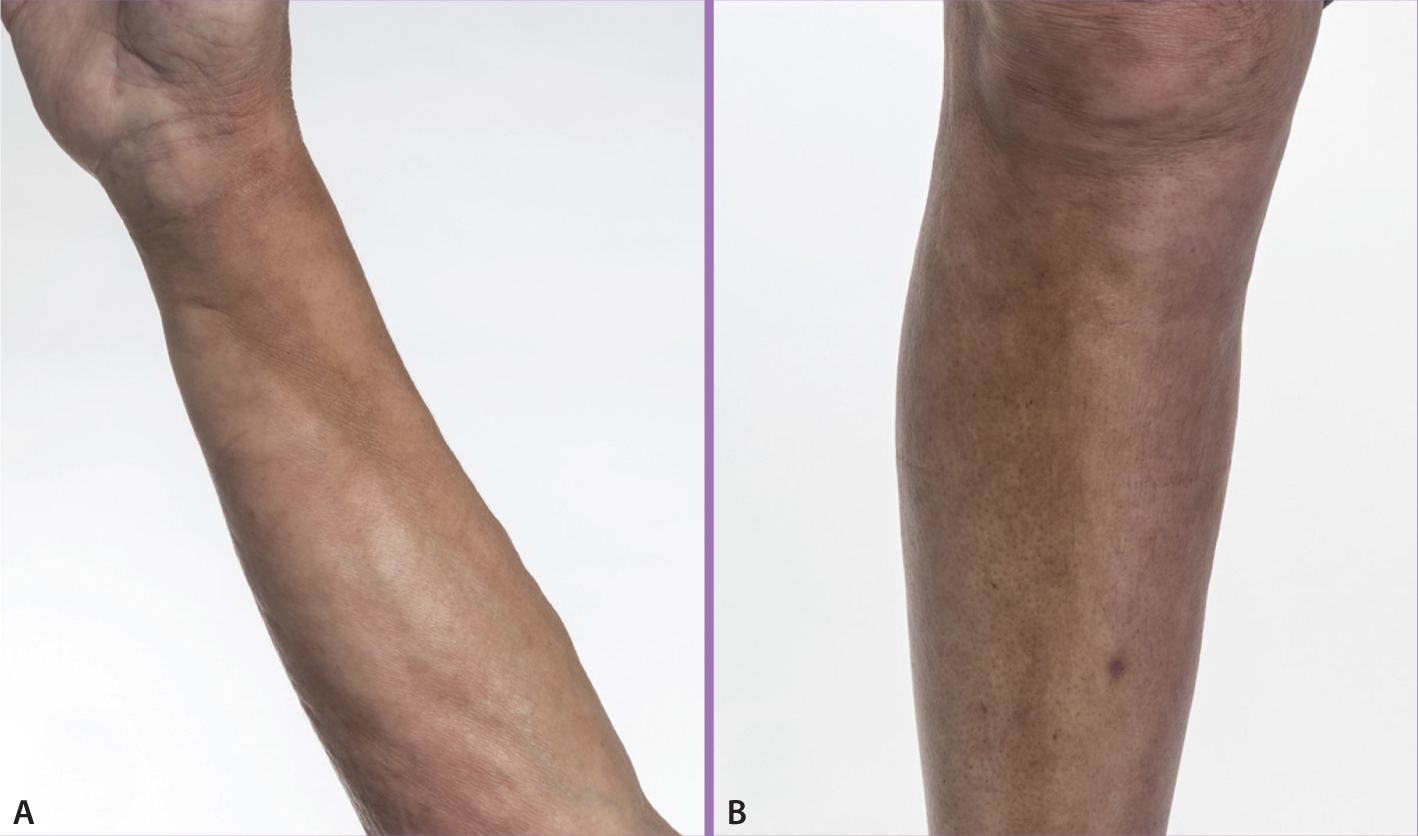

Dellen und Flecken an Armen und Beinen

Bräunliche Verfärbungen und Indurationen der Haut an Vorderarmen und Schienbeinen.

Ein 64-jähriger Mann stellte sich mit Weichteilschwellungen sowie bräunlichen Verfärbungen und Indurationen der Haut an seinen Vorderarmen sowie den Schienbeinen in einer rheumatologischen Ambulanz vor (Abb. A, B). Ein Labortest zeigte eine moderat erhöhte humorale inflammatorische Aktivität mit erhöhten Konzentrationen von C-reaktivem Protein (CRP) von 30 mg/l (Normalwert: < 3) und eosinophilem kationischem Protein (ECP) von 95,1 μg/l (Norm: 13,3) sowie einer Eosinophilie von 2.200 Granulozyten/μl (Norm: < 450).